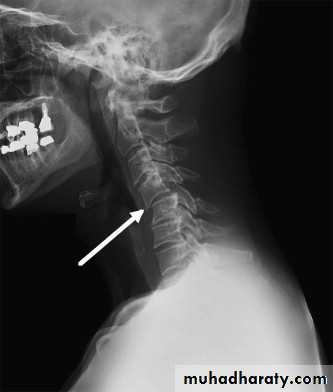

DIAGNOSISX RAY

Anterio posterior X ray radiograph.lateral radiographs with the head in flexion and extension may revealinstability that is not shown in the routine lateral film.

oblique views

at 45° are especially helpfula special projection

SOFT-TISSUE STRAIN OF THE CERVICAL SPINE

Mechanism of injury and pathology

At the moment of impact, the head is firstsuddenly jolted forwards followed by rebound flexion of the spine.

And a second by extension of the neck.